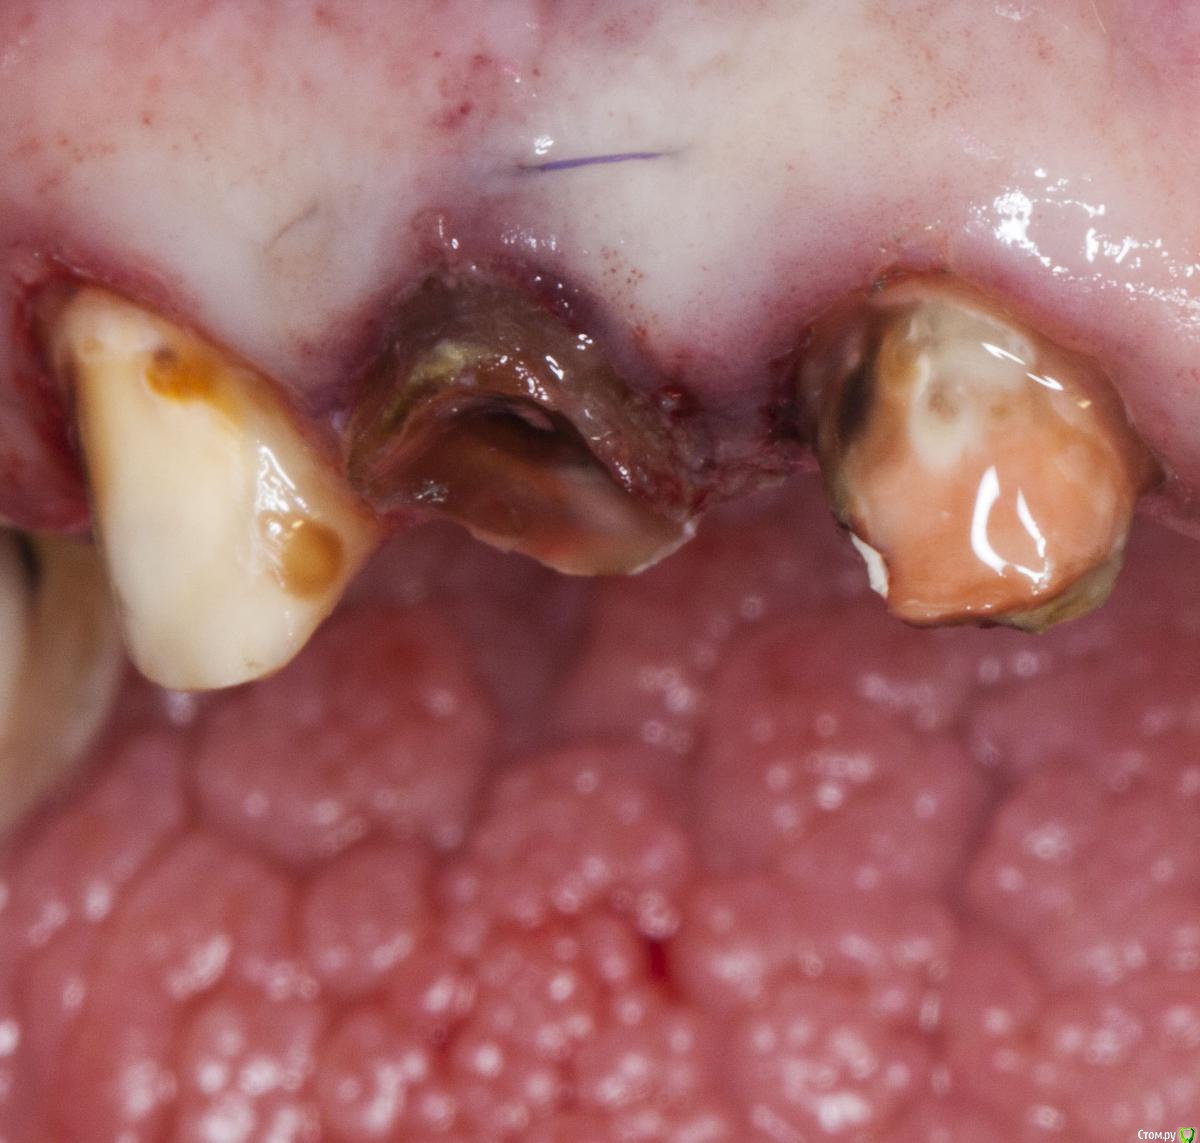

Денис777 Опубликовано 25 марта, 2015 Автор Поделиться Опубликовано 25 марта, 2015 Потому,что дистальный корень этого зуба разрушен до уровня кости .. Ссылка на комментарий

Bratok Опубликовано 26 марта, 2015 Поделиться Опубликовано 26 марта, 2015 С этим зубом можно сделать многое, но эндодонтический и реставрационный прогноз неблагоприятный по данному снимку.Обычно для того, чтобы дать долгосрочный прогноз нужно смотреть динамику после всех лечебных мероприятий. 6-8 месяцев, потом через 2-4 года. Ссылка на комментарий

Megadeth Опубликовано 26 марта, 2015 Поделиться Опубликовано 26 марта, 2015 я бы удалял. но как вариант извлечь вкладку, удалить дистальный корень, перепломбировать мед. каналы, новая вкладка и коронка с подвесом. Ссылка на комментарий

M@estro Опубликовано 26 марта, 2015 Поделиться Опубликовано 26 марта, 2015 так просто проще...и дороже + . И это печально.. Не проходит и дня, как ко мне попадает пациент с диагнозом " кеста зуба" или " сложный случай" (с) . Это банальные кейсы с феруллом, я уж молчу про такое : 1 Ссылка на комментарий